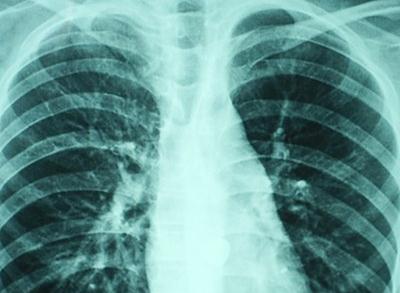

5.X線胸片:大片狀陰影,多見肺底和中部,個(gè)別為粟粒狀陰影,但在短期內(nèi)可有變化。

8.臨床癥狀輕而肺部X線征象嚴(yán)重;使用抗生素,病勢(shì)惡化;用抗真菌藥物治療顯效。